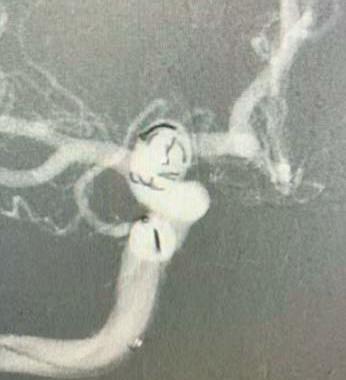

As per an observational study published in the journal Neurology last year, female hormone therapy use may be associated with a higher risk of intracranial haemorrhage from cerebral cavernous malformations (CCMs)—raising questions about the safety of these therapies for CCM patients in clinical practice. Here, study authors Alejandro Santos and Philipp Dammann (both Essen, Germany) attempt to elucidate the wider implications of their findings.

CCMs can lead to seizures and neurological deficits due to intracranial haemorrhage, or nonhaemorrhagic focal neurological injury. The pathophysiology leading to stroke due to intracranial haemorrhage in patients with a CCM is still unclear, but some theories exist based on previous research. It is believed that the latter might be triggered by clot formation in the dilated vessels of the CCM through which the blood flows very slowly.

To this end, the University Hospital of Essen in Germany recently performed an observational cohort study with longterm follow-up in collaboration with the Mayo Clinic (Rochester, USA) to investigate such associations.

Both clinics included consecutive patients with a CCM being followed in their respective departments, and compared the association between use of female hormone therapy and the occurrence of intracranial haemorrhage due to the CCM across up to five years of prospective follow-up. Out of a cohort of 722 female patients, aged 10 years or older at time of CCM diagnosis, 137 used female hormone therapy at any point during follow-up.

This study showed that female hormone therapy use was associated with an increased risk of subsequent intracranial haemorrhage and, moreover, that the use of oral contraceptives in female patients aged 10–44 years was associated with an even higher risk of subsequent intracranial haemorrhage.

Therefore, the rationale of having increased blots clots in the caverns of CCMs in patients under female hormone therapy—which might subsequently lead to higher rates of bleeding—is reasonable.

Female hormone therapy—oral contraception in females of reproductive age and menopausal hormone therapy in postmenopausal females—has been shown to increase the risk of stroke and venous thrombosis. Yet, the latter is not withheld from patients with CCMs. The effects of these drugs on the risk of intracranial haemorrhage are also unknown.